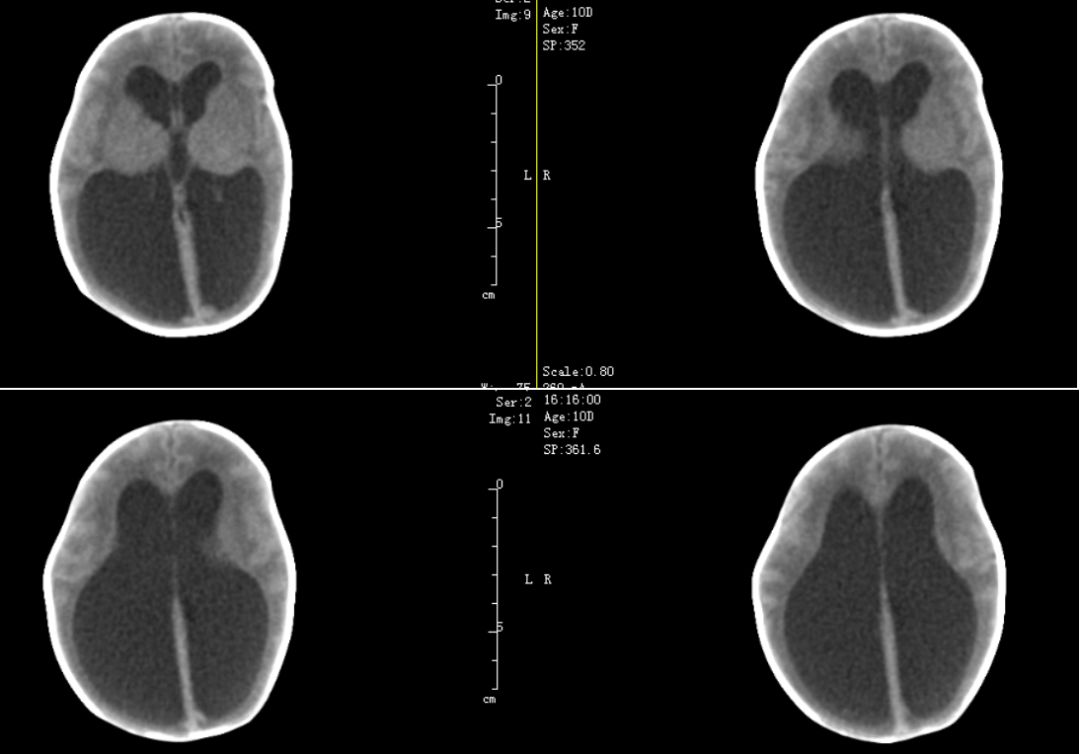

患儿1,女,10天,因“早产后被人发现10天,发现脑积水7天”于2012年11月13日入院。

患儿系弃婴双胞胎之一,出生史不详,10天前因发现被遗弃于当地妇幼保健院,予收治住院治疗,当时胎龄评估33周,体重1220g,予抗感染、营养对症支持治疗。2012.11.6头颅B超示脑积水。后复查头颅B超示脑积水较前加重,遂转来我院。

入院查体:体温36.3度,脉率152次/分,呼吸50次/分,血压67/31mmHg,体重1560克,身长41厘米,头围32.5厘米,胸围23.0厘米,反应尚可,早产儿貌,前囟5*5 cm,隆起,骨缝分离。听诊心律齐,未及杂音,二肺呼吸音粗,未及罗音,腹软、膨隆,肝肋下1cm,脾肋下未及。肌张力正常,生理反射减弱。

辅助检查:2012.11.06头颅B超示脑积水:左侧脑室扩张最宽约2.6cm,右侧脑室扩张最宽约2.4cm。11.13头颅B超示重度脑积水:左侧脑室扩张4.5cm,右侧脑室扩张4.7cm,第三第四脑室扩张约0.8cm。11.13急诊血常规:WBC:19.37×10^9/L,N:55.6%,HB:120 g/L,PLT:297×10^9/L,CRP:3mg/L。

患儿2,女,系上述弃婴双胞胎之二,体重1280g,查头颅B超示重度脑积水。也转来我院。

查体:体温36.1度,脉率156次/分,呼吸52次/分,血压51/23mmHg,经早产儿奶喂食等后,体重增长至1.4kg。身长42厘米,头围31.0厘米,胸围27.0厘米,反应差,早产儿貌,面色苍白,前囟饱满,约3*3cm,颅骨缝明显增宽。听诊心律齐,心前区可及II/6杂音,二肺呼吸音稍粗,未及罗音,腹软,肝肋下1cm,质软,脾肋下未及。肌张力减弱,生理反射减弱。

辅助检查:2012.11.13头颅B超示重度脑积水:左侧脑室扩张最宽2.7cm,右侧脑室扩张最宽约2.7cm,第三脑室扩张约0.5cm。11.13门诊血常规:WBC19.05*10^9/L,N:37.0%,HB:135g/L,PLT:268×10^9/L,CRP:<1mg/L。

科室讨论:两例患儿为弃婴双胞胎,出生史胎龄不详,低体重儿,仅1560g和1410g,B超发现脑室扩大,腰穿结果均为淡黄色,无明显感染迹象,CT和MR提示重度脑积水,导水管以上脑室扩张明显,四脑室正常,未见明显占位病变,考虑先天性发育畸形引起的中脑导水管狭窄,不排除新生儿脑室内出血后继发性导水管梗阻或狭窄可能,建议动态观察头围变化和监测B超,间断行腰穿释放脑脊液降低颅内压,有进行性加重可考虑手术干预。

病例1,治疗观察2周后头围较前明显增大,由32.5cm增大至35.0cm,体重由1560g增长至1840g,查B超提示左侧脑室体宽4.42cm,右侧脑室体宽4.95cm,第三脑室扩张约1.1cm。侧脑室形态不规则,B超测量取决层面差异,三脑室有增大情况,考虑脑积水,遂决定行脑室腹腔分流术。

病例2治疗观察2周后复查头围较前变化不大,由31.0cm增加至32.5cm,体重由1410g增加至1910g,查B超提示:左侧侧脑室体宽2.9cm,右侧体宽2.4cm,第三脑室宽1.0cm,有进行性增大趋势,也决定行VP分流术。

目前两例患儿总体生长发育情况良好,未见明显的神经功能后遗症情况,但未进行系统性评估。